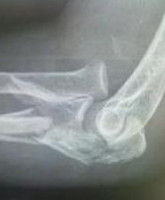

1.X線肘關節側位像 因無移位骨折在正位像上往往表現不出。

2.雙側X線攝片對比 肘關節化骨中心在融合前有可能與骨折混淆,可疑者應攝健側對比。

1.X線肘關節側位像因無移位骨折在正位像上往往表現不出。2.雙側X線攝片對比肘關節化骨中心在融合前有可能與骨折混淆,可疑者應攝健側對比。